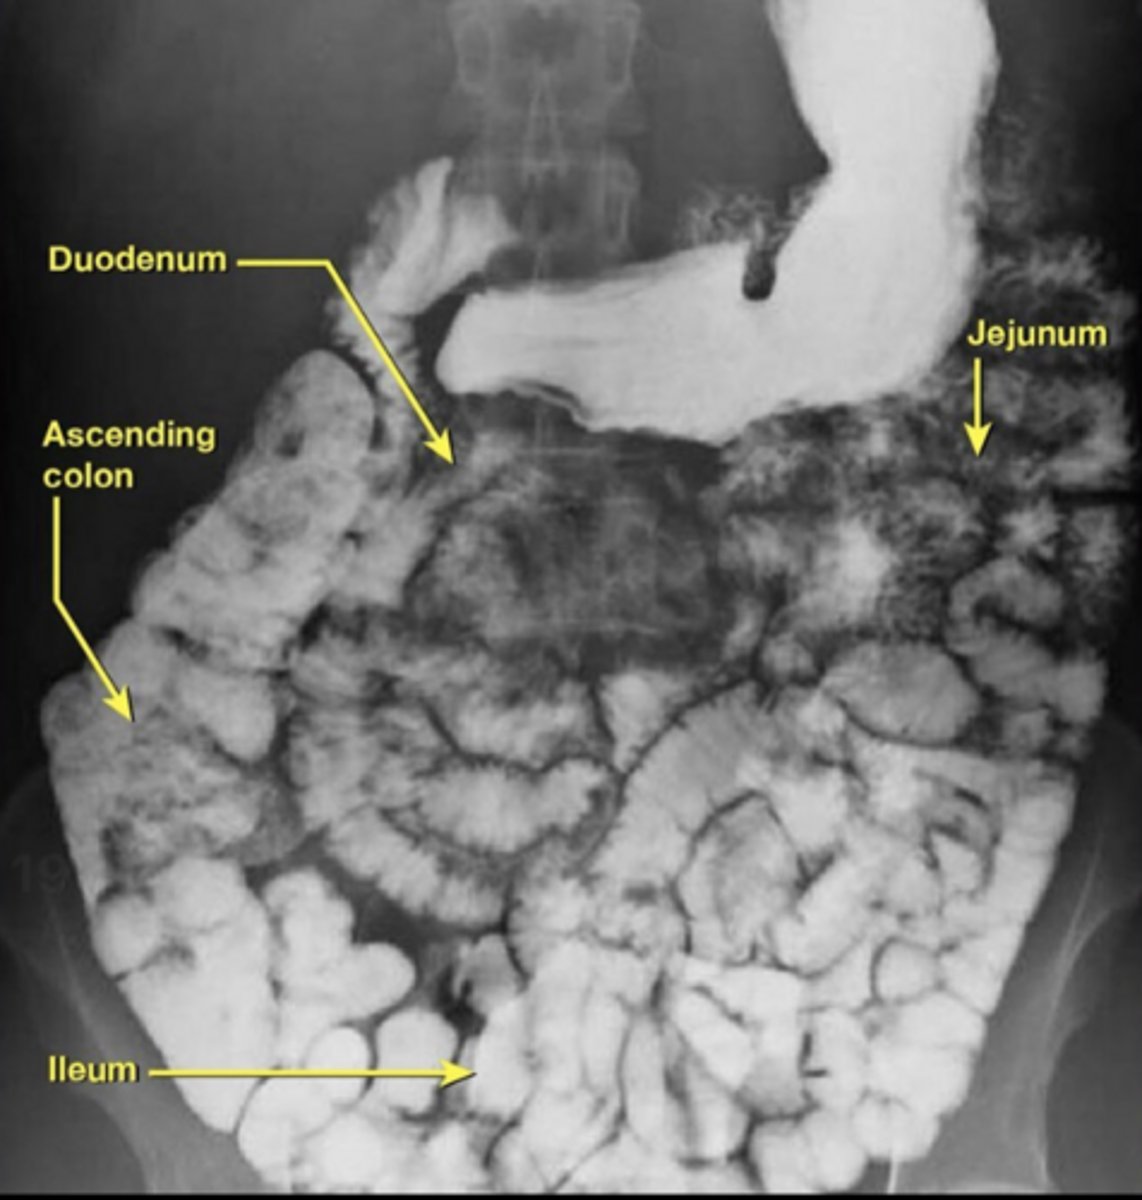

duodenum, jejunum, ileum (DJI)

What are the four parts of the duodenum?

How do you identify the duodenojejunal junction on imaging?

Located left of midline at ligament of Treitz where bowel becomes intraperitoneal jejunum.

How can you distinguish jejunum from ileum anatomically?

Jejunum has a larger diameter, numerous mucosal folds, long vasa recta, and fewer arterial arcades.

Ileum has a smaller diameter, fewer folds, short vasa recta, and more complex arcades.

On imaging, how do you distinguish jejunum from ileum?

Jejunum shows thick walls and numerous folds; ileum has smoother walls and fewer folds.